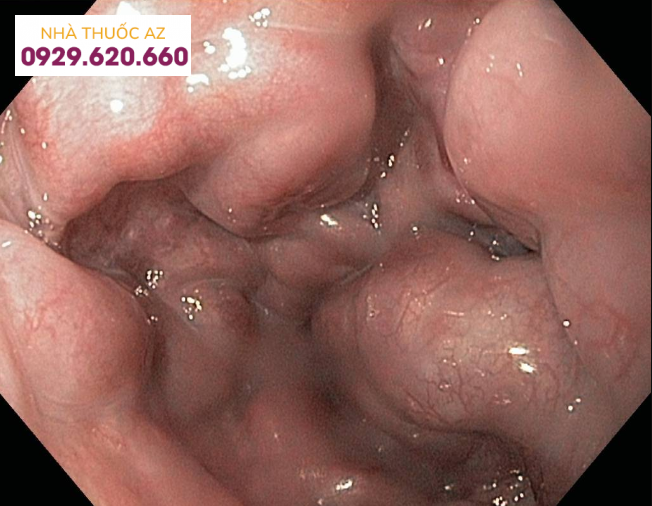

Giãn tĩnh mạch thực quản được phát hiện bằng nội soi

Giãn tĩnh mạch thực quản có mấy độ được phân cấp theo kích thước của các búi giãn tĩnh mạch.

Độ 1 – Nhỏ: Các búi giãn tĩnh mạch thực quản thẳng và nhỏ.

Độ 2 – Trung bình: Các búi giãn tĩnh mạch có kích thước tương đối lớn, có hình dáng xâu chuỗi và chiếm diện tích khoảng trên 1/3 trong lòng thực quản. Khi bơm hơi, các búi giãn không bị xẹp.

Độ 3 – Lớn: Các búi giãn tĩnh mạch có kích thước lớn, có hình dáng giống khối u và chiếm diện tích trên 1⁄3 trong lòng thực quản.

Tuy nhiên, Hiệp hội Nghiên cứu các bệnh về gan Hoa Kỳ (AASLD) đã đưa ra khuyến cáo nên phân cấp độ giãn tĩnh mạch thực quản thành 2 cấp độ là nhỏ (kích thước búi giãn <5mm) và lớn (kích thước búi giãn >5mm) do tỷ lệ các búi giãn tiến triển từ nhỏ đến lớn tương đối cao (7%/năm).